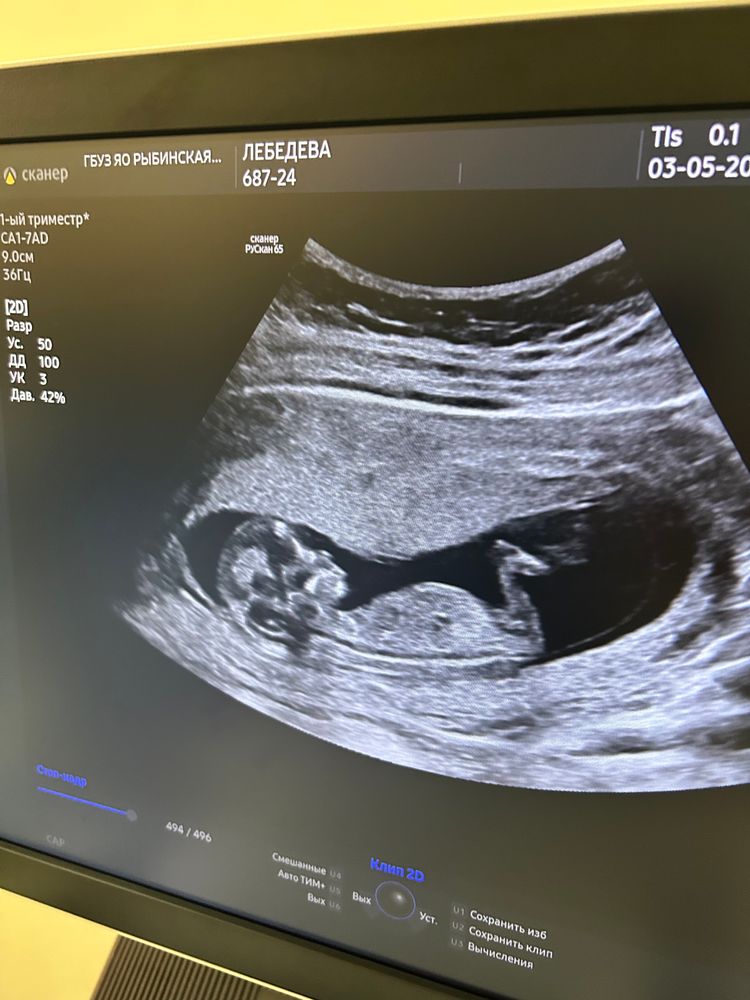

Первый скрининг 💗посмотрели нашего человечка.

кстати, предположительно пол сказали. Как думаете, кто на фото?)